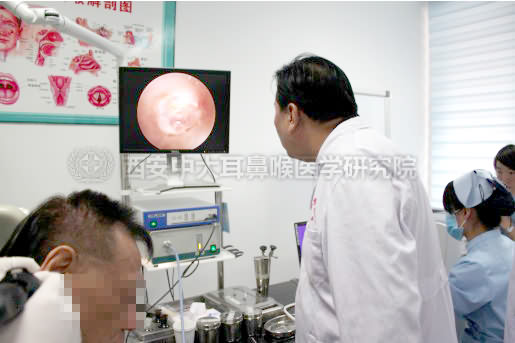

图为可将耳部病灶放大500倍成像的耳内窥镜